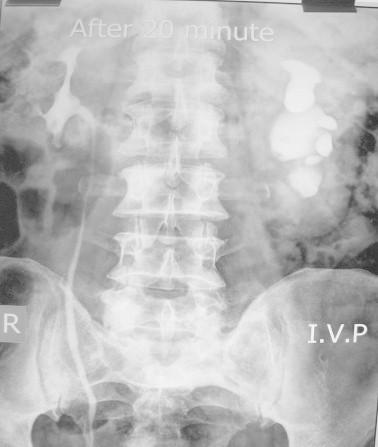

We identified 19 reports of major clinical significance and reviewed them. As in the cases from our institution, supraclavicular lymphadenopathy, isolated upper ureteric obstruction and severe obstructing constipation were some of the rare presentations encountered at other institutions, and reported mostly as sporadic case-reports.

我们确定了19篇具有主要临床意义的报告并进行了综述。与我们机构的病例一样,锁骨上淋巴结病、孤立性上输尿管梗阻和严重梗阻性便秘是其他机构遇到的一些罕见表现,大多作为散发病例报告。